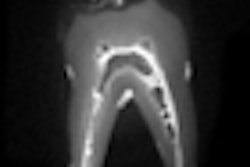

The new RVG 6500 features the Intelligent Positioning System (IPS) that ensures accurate sensor placement during patient examinations by visually aiding alignment of the sensor with an intuitive, real-time display, according to the company. Once the generator's x-ray beam is correctly aligned with the sensor, the IPS automatically notifies the user.

The RVG 6500 system is also Wi-Fi-enabled and the design allows the user to adapt the system to various practice configurations, accommodating both multisensor and multicomputer environments.